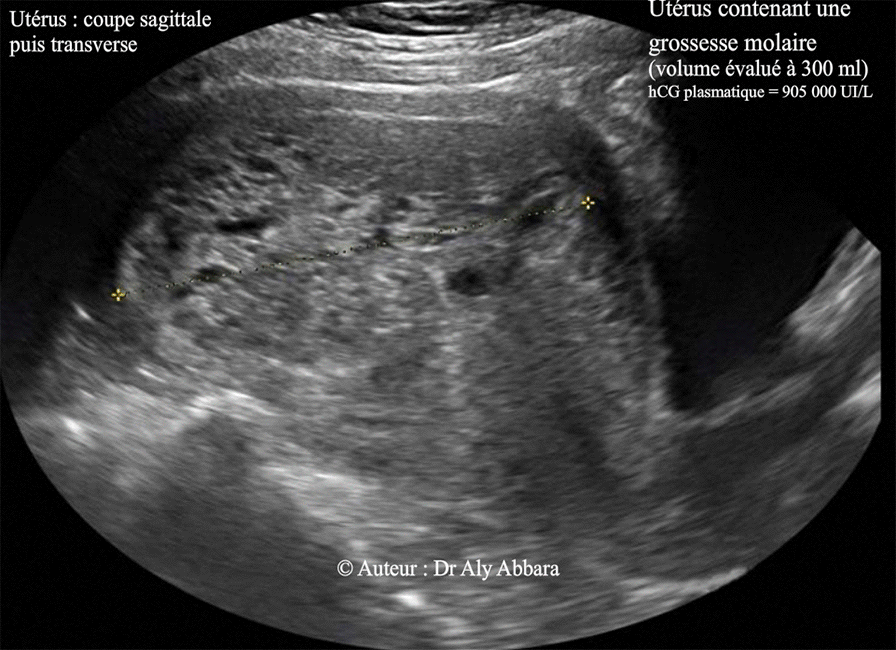

Grossesse môlaire -Môle complète de 300 cc de volume - Aspect échographique

• Images échographiques et macroscopiques d'une grossesse molaire de 11 SA

• L'échographie par voie transpariétale abdominale montre une cavité utérine occupée par une structure tissulaire, hétéro-échogène, parfois vésiculaire et sans aucun élément anatomique embryonnaire ou fœtal reconnaissable ; sans cavité amniotique et sans vésicule vitelline. Le Doppler montre très peu d'activité circulatoire sanguine au sein de cette structure dont le volume a été évalué à 300 ml.

• Biologiquement, le taux de β-hCG plasmatique était très élevée, à 905 000 UI/ml.